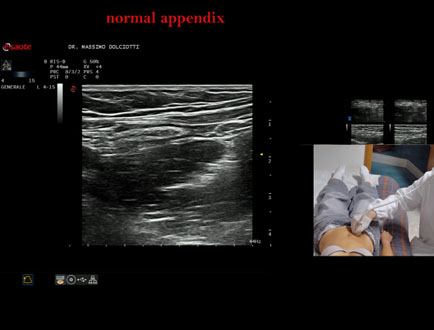

Data inserimento: 26/09/2025

Ecografia del: 12/09/2025

Strumento: Esaote MyLab Eight

Sonda: Lineare Multifrequenza 4-15 MHz

Età Paziente: F 24 anni

Motivazione dell'esame: da 3 mesi dolore al fianco destro.

Commento all'esame: le immagini ed il video documentano l'appendice di spessore normale (5,1-5,7 mm - v.n. < 6 mm).

Conclusioni: appendice normale (normal appendix).

Presentazione: Dr. Massimo Dolciotti - Ancona

Elaborazione digitale: Andrea Dini - Ancona